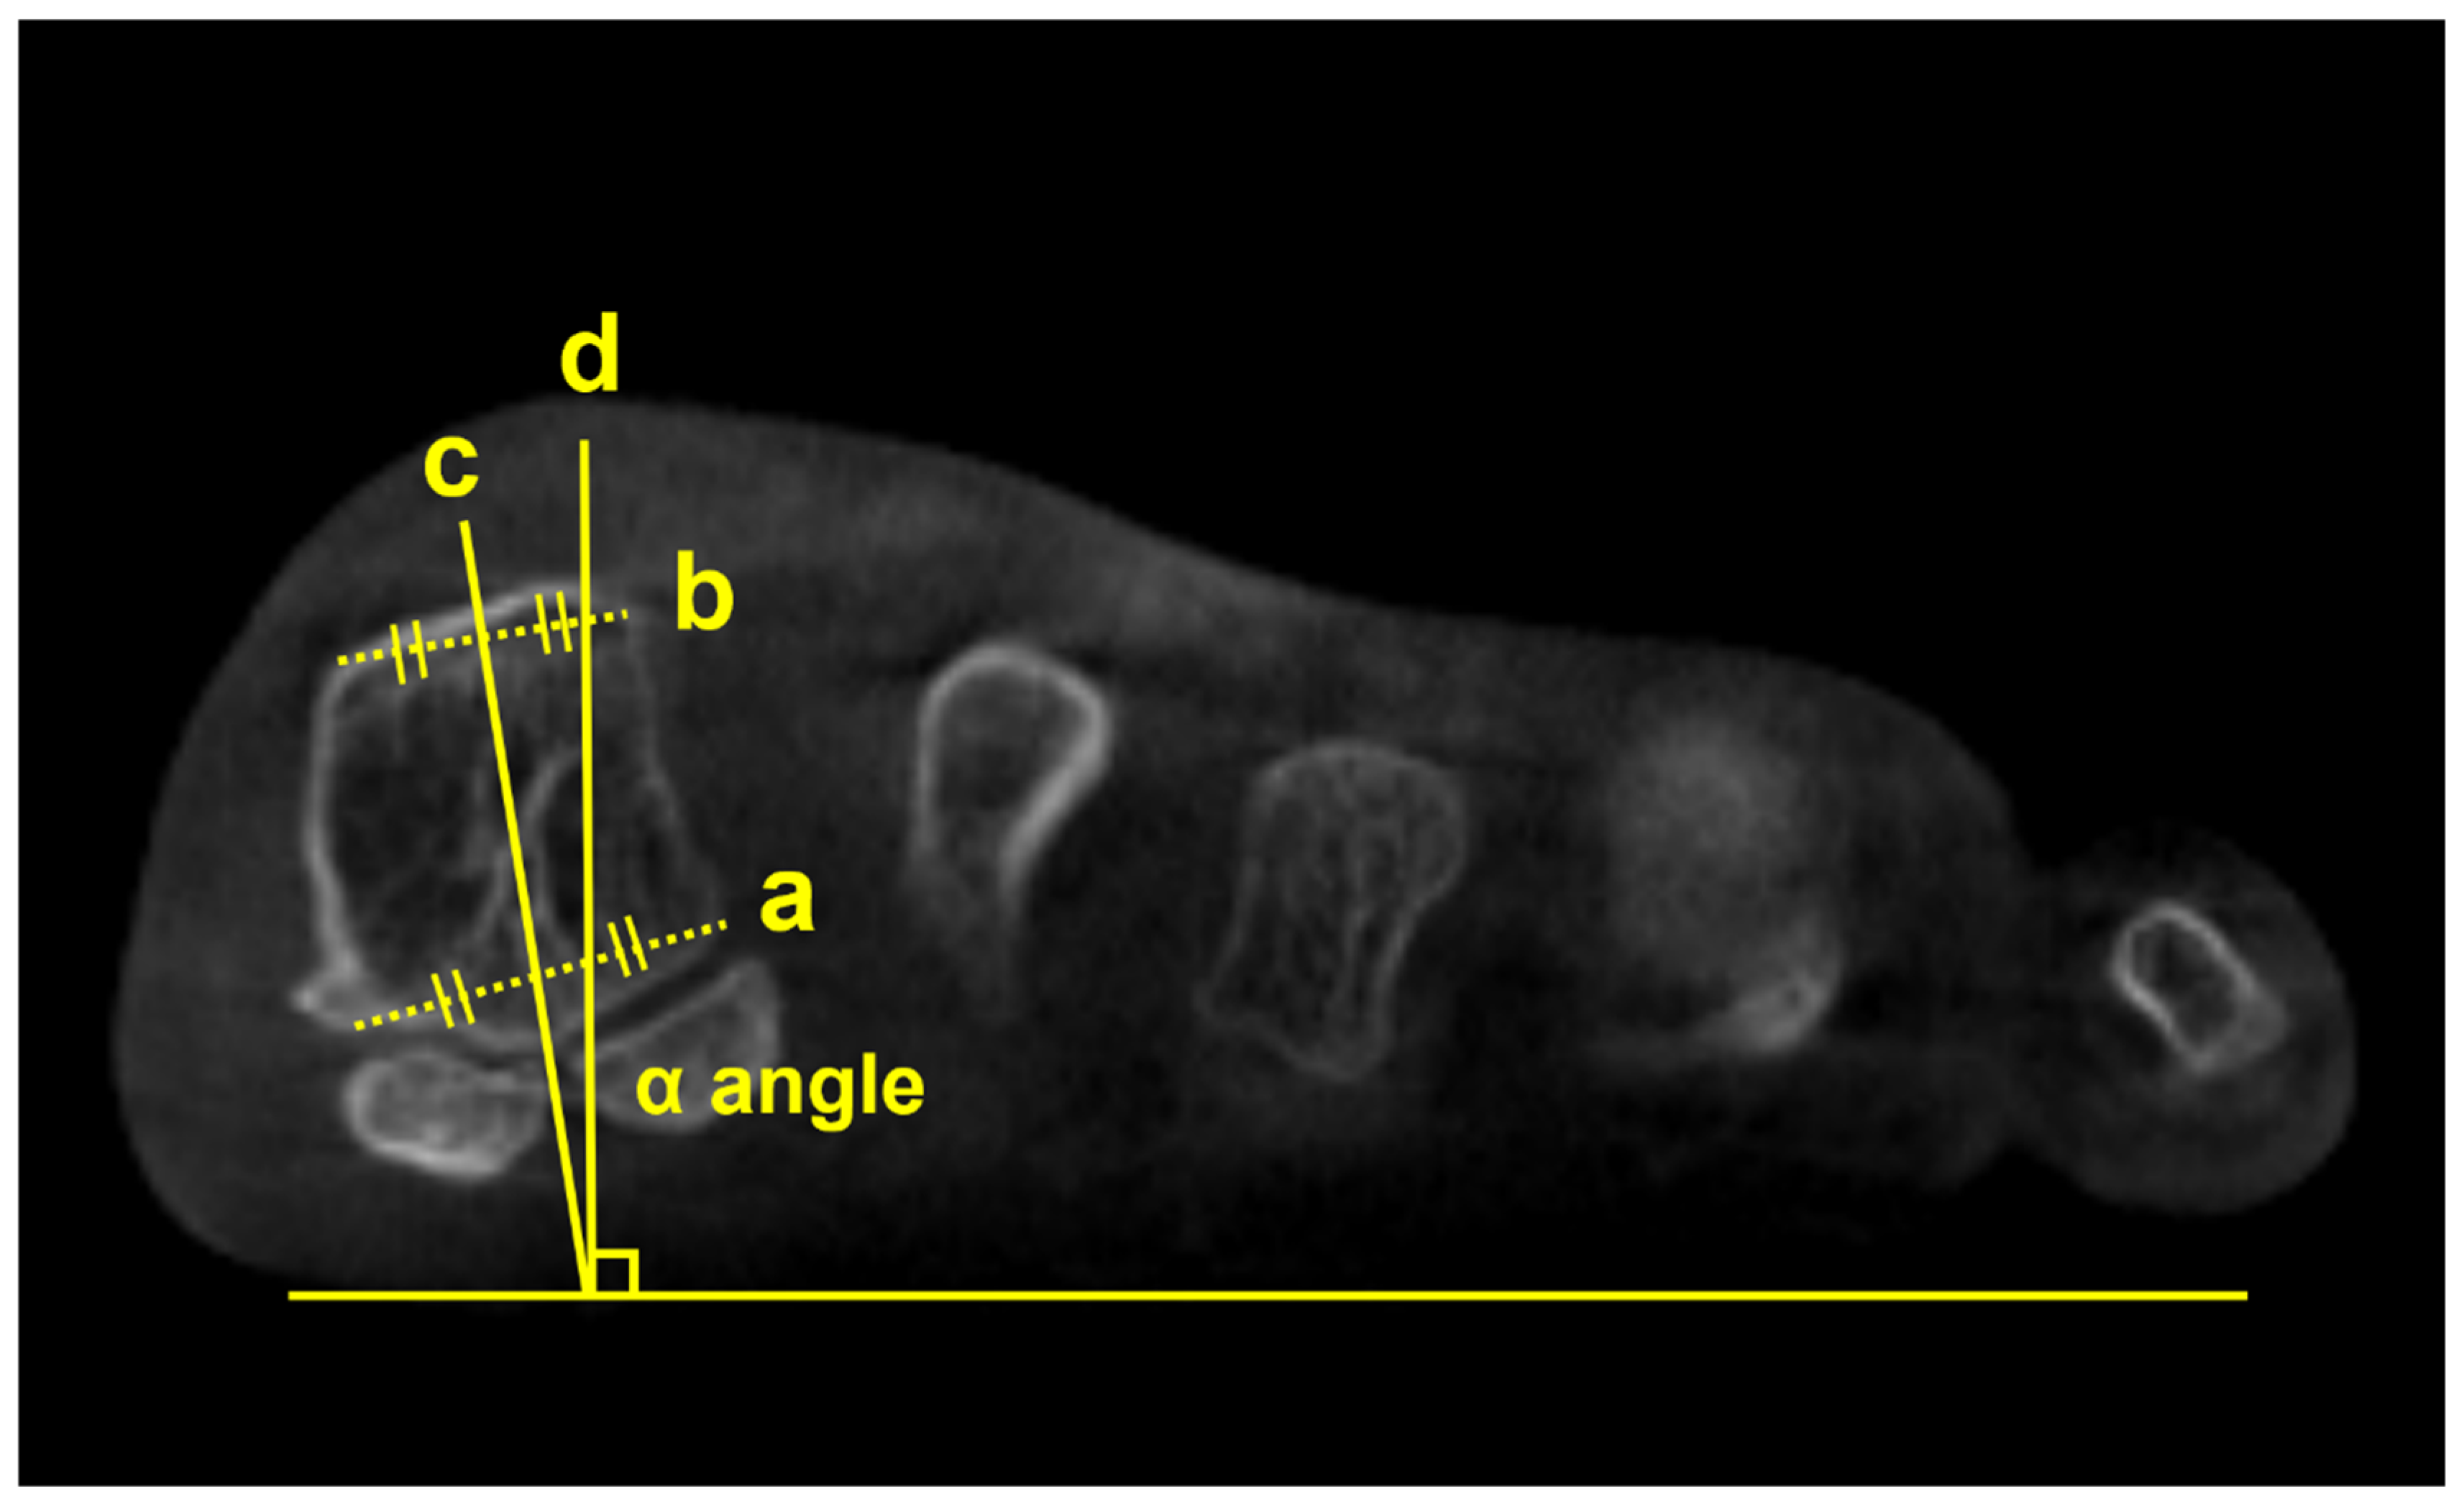

Using a semi-weightbearing CT, Kim et al devised the alpha angle to evaluate the pronation of the M1 [11]. It was determined on the axial view by measuring the angle between the line bisecting the M1 and the vertical line perpendicular to the horizontal ground axis (Figure 2). Authors reported that 87.3% of the patients with hallux valgus had a more pronated M1 than the control group, with a greater alpha angle. Similarly, Campbell et al measured the M1 rotation with 3D geometrically determined angles and found that M1 pronation relative to second metatarsal was 8.2 degrees greater in the hallux valgus group than in the control group [12]. Furthermore, Mansur et al used WBCT to verify the round sign, an indirect sign of M1 pronation in conventional radiographs, and concluded that round sign weakly correlated with the alpha angle measured on WBCT [13]. Overall, these findings suggest that it is challenging to fully recognize the complex 3D deformities of hallux valgus using only conventional radiographs and incorporation of WBCT would be beneficial.

Figure 2. To obtain the alpha (α) angle, first, an inferior line is drawn between the lateral edge of the lateral sulcus and the medial edge of the medial sulcus (a). Subsequently, a superior line is drawn between the point of the medial and lateral corners of the first metatarsal head (b). Second, bisections of the above 2 lines are connected to a straight line perpendicular to the horizontal ground axis (c). Third, the angle is measured between the straight line (c) and the vertical line perpendicular to the ground axis (d) that is obtained from the first step.